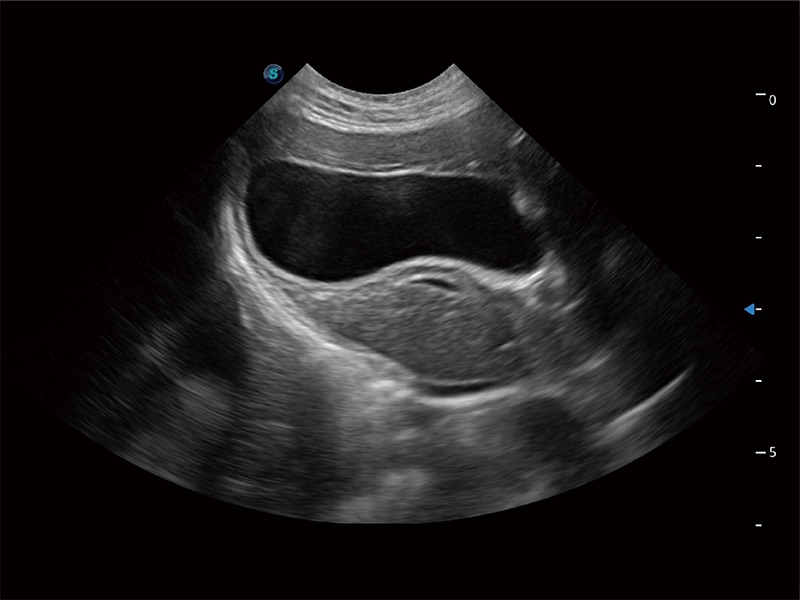

动物是人类最亲密的朋友和最值得信赖的伙伴。db真人体育官网也一直致力于探索动物专用的超声影像解决方案。全新推出的ProPet系列,是db真人体育官网在动物超声影像智能化、专业化、精准化的一次跨越式革新。动物不能用言语来表述自己的不适,通过超声影像,ProPet系列搭建了动物医生与不同物种沟通的“桥梁”,为动物医生注入了“治愈之力”。 ProPet 80 是db真人体育官网匠心打造的一款高端动物专用彩超,采用性能卓越的全新硬件架构,极大提升超声系统的运行效率和数据处理能力,帮助动物医生从容应对日益增多的挑战性病例和日益多样化的临床需求。

高性能和先进的临床应用工具可以为动物医生提供临床信心。ProPet 80 搭载了先进的腹部和浅表应用工具,帮助医生在日常临床实践中发挥前所未有的作用。

一键自动识别膀胱壁及自动测量膀胱容积,不受膀胱形状和大小的限制,帮助医生快速精准获得测量的数据。